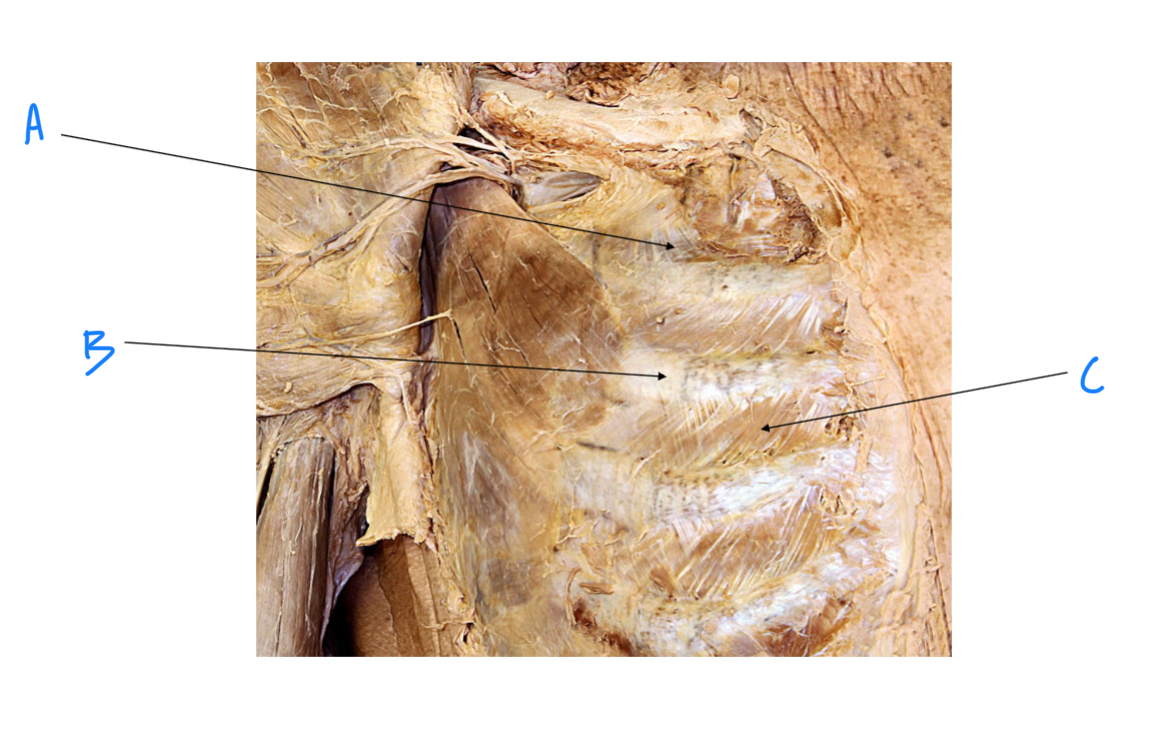

A. Identify structure

Transverse foramen; Vertebral a.

B. Identify structure; What goes through this feature?

Transverse process

C. Identify structure